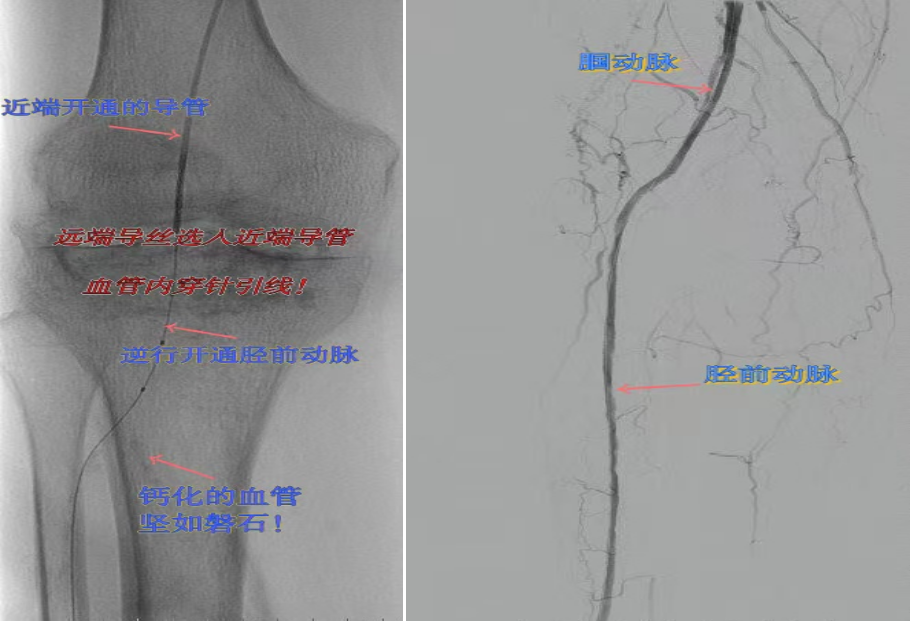

67岁女性患者,多年糖尿病、冠心病史,因右足溃烂伴凉麻疼痛长达2年就诊,此前曾接受外院介入术后血管再度闭塞。此次检查发现其股浅动脉、腘动脉至膝下血管全程闭塞,且伴有严重钙化。团队迎难而上,创新性经足背动脉逆向穿刺,耗时3小时成功贯通胫前动脉。术后当夜患者足部即感回暖,溃烂足趾疼痛显著缓解。术后结合中药外治(换药、熏洗、去腐生肌膏外敷)加速创面愈合。该患者已于出院,院外换药治疗。

影像检查:股浅动脉、腘动脉至膝下血管全程闭塞伴严重钙化。

两例患者共同凸显三大高难度治疗挑战:1.患者高龄且基础病复杂;2.血管全程多节段闭塞、钙化程度严重;3.常规顺向开通路径已被完全阻断。团队果断采用远端逆行穿刺技术,在纤细的足踝部血管建立治疗通道,实现“逆向破冰”。